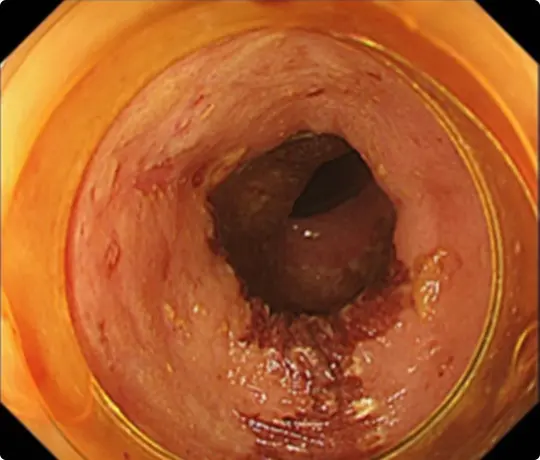

約3cmの大きな大腸ポリープです。

スネアでポリープの根元を縛り、電流を流して切除します(出血予防のためポリープの根元にクリップをうっています)。

切除した検体です。病理検査で早期大腸がんと診断されました。がんは完全に切除されており、治癒と判定されました。